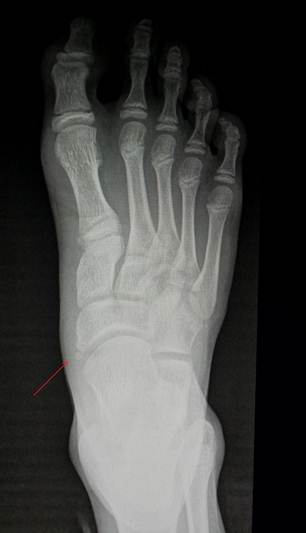

Слева

прямой снимок стопы ребенка 12 лет, апофиз ладьевидной кости тольок начал

прослеживаться (помечен красной стрелкой). Справа прямой снимок стопы ребенка

16 лет, полное срастание апофиза ладьевидной кости с основным костным массивом.

Красной линией отмечена локализация зоны просветления, которая наблюдается в

случае формирования os tibiale externum.